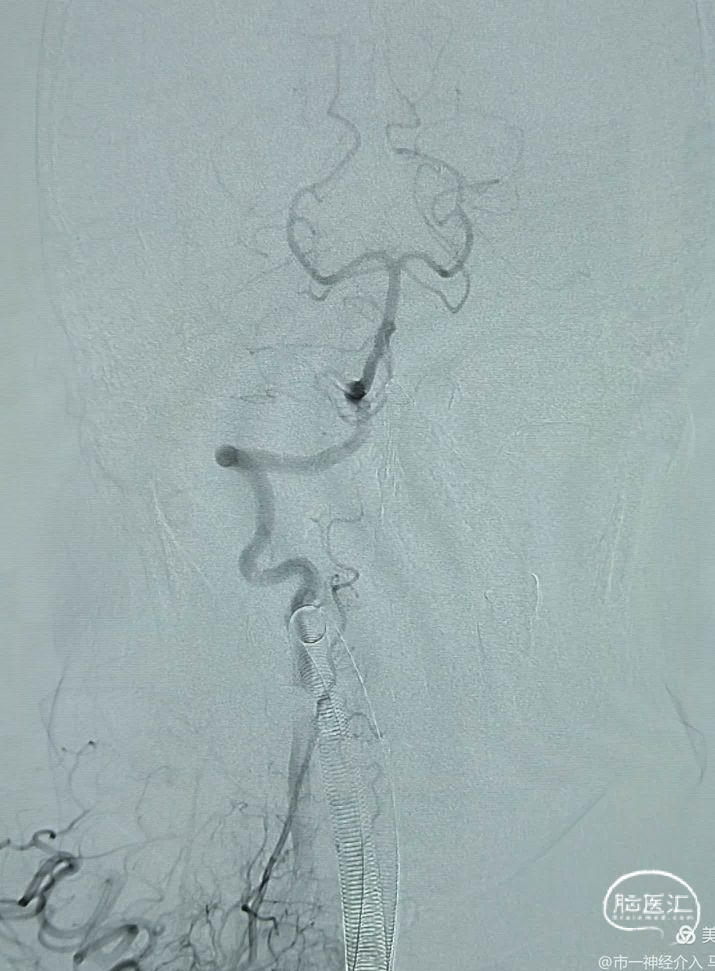

数枚弹簧圈进去,载瘤动脉及动脉瘤致密栓塞,小脑后下动脉显影良好,且有侧支与基底动脉近端联通。

术后用导引导管到右侧锁骨下动脉造影,显示右侧椎动脉、基底动脉及远端的各重要分支血流通畅,手术用时不足半小时,麻醉醒后患者无任何神经功能缺损表现,住院一周后回广东了,嘱咐患者三个月后在当地医院复查。